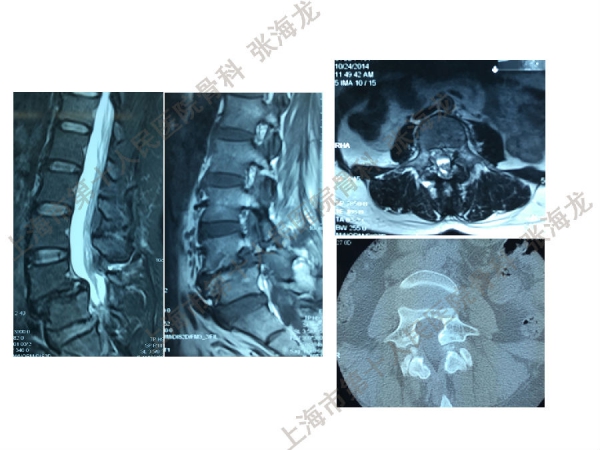

2008年3月至2010年8月,上海市第十人民医院骨科随访49例腰椎滑脱症(峡部裂型和退变型)患者,对比23例微创手术MIS-TLIF和26例开放手术治疗腰椎滑脱症的临床及影像学结果,进行了回顾性研究。

研究发现,Wiltse入路Mis-TLIF更直接的暴露峡部及关节突,对脊柱稳定性的影响较小;彻底松解辅助双重提拉复位Mis-TLIF,对于峡部裂型滑脱有较好的复位效果;对于峡部裂型滑脱,提拉复位在影像学参数上有一定优势;与原位融合相比,ODI.VAS.JOA无明显差异(样本量有限);对于退变性滑脱,单纯撑开椎间隙与原位融合可以获得较好疗效。